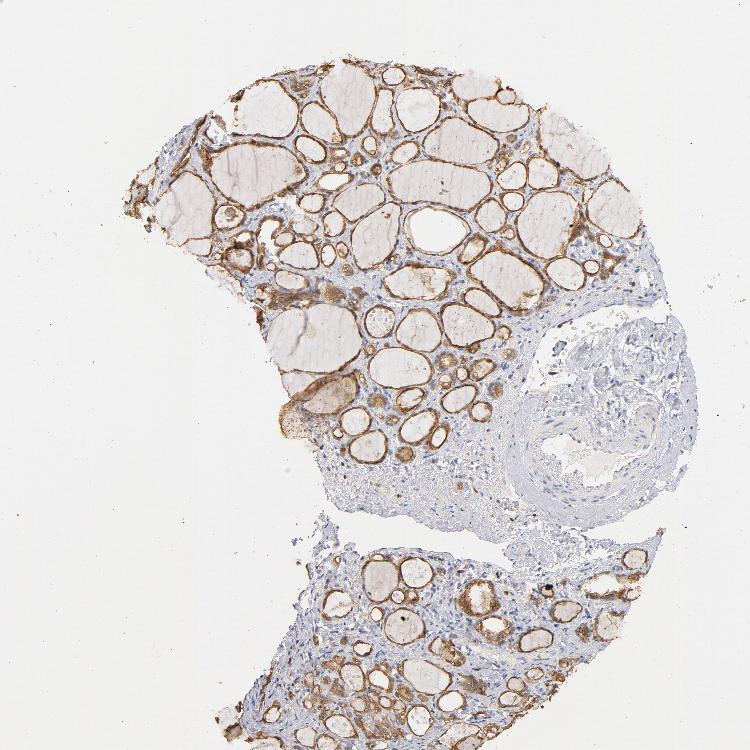

THYROID GLAND - Antibody stainingi

Antibody staining in the annotated cell types in the current human tissue is reported as not detected, low, medium, or high, based on conventional immunohistochemistry profiling in selected tissues. This score is based on the combination of the staining intensity and fraction of stained cells.

Each image is clickable and will lead to virtual microscopy that enables deeper exploration of all samples and also displays staining intensity scores, fraction scores and subcellular localization as well as patient and tissue information for each sample.

Antibody HPA021616Antibody CAB004035Antibody CAB047324Antibody CAB075739

Glandular cells MediumMediumHighMedium